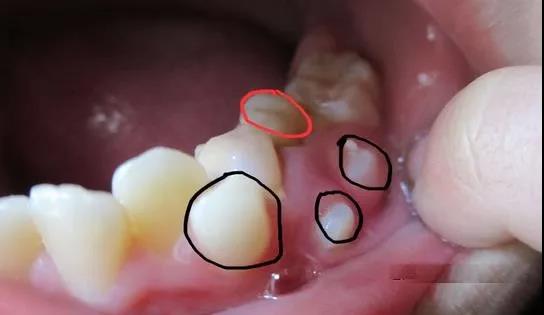

一部分孩子的两个门牙会出现异常的多生牙或者上唇系带附着过低等造成的门牙之间间隙过大的情况,是不会自行消失。多生牙指在牙齿发育时,牙齿的数量比正常情况多。多生牙大多位于两上门牙之间,会影响两个门牙间缝隙的正常闭合,应当及时检查及治疗。

“锯齿状”门牙怎么回事?

新换的门牙刚萌出时呈锯齿状。“锯齿”是牙齿的发育结节,随着年龄的增长,牙齿会因为咀嚼和对合牙的咬合逐渐磨耗,缓慢变得平整。